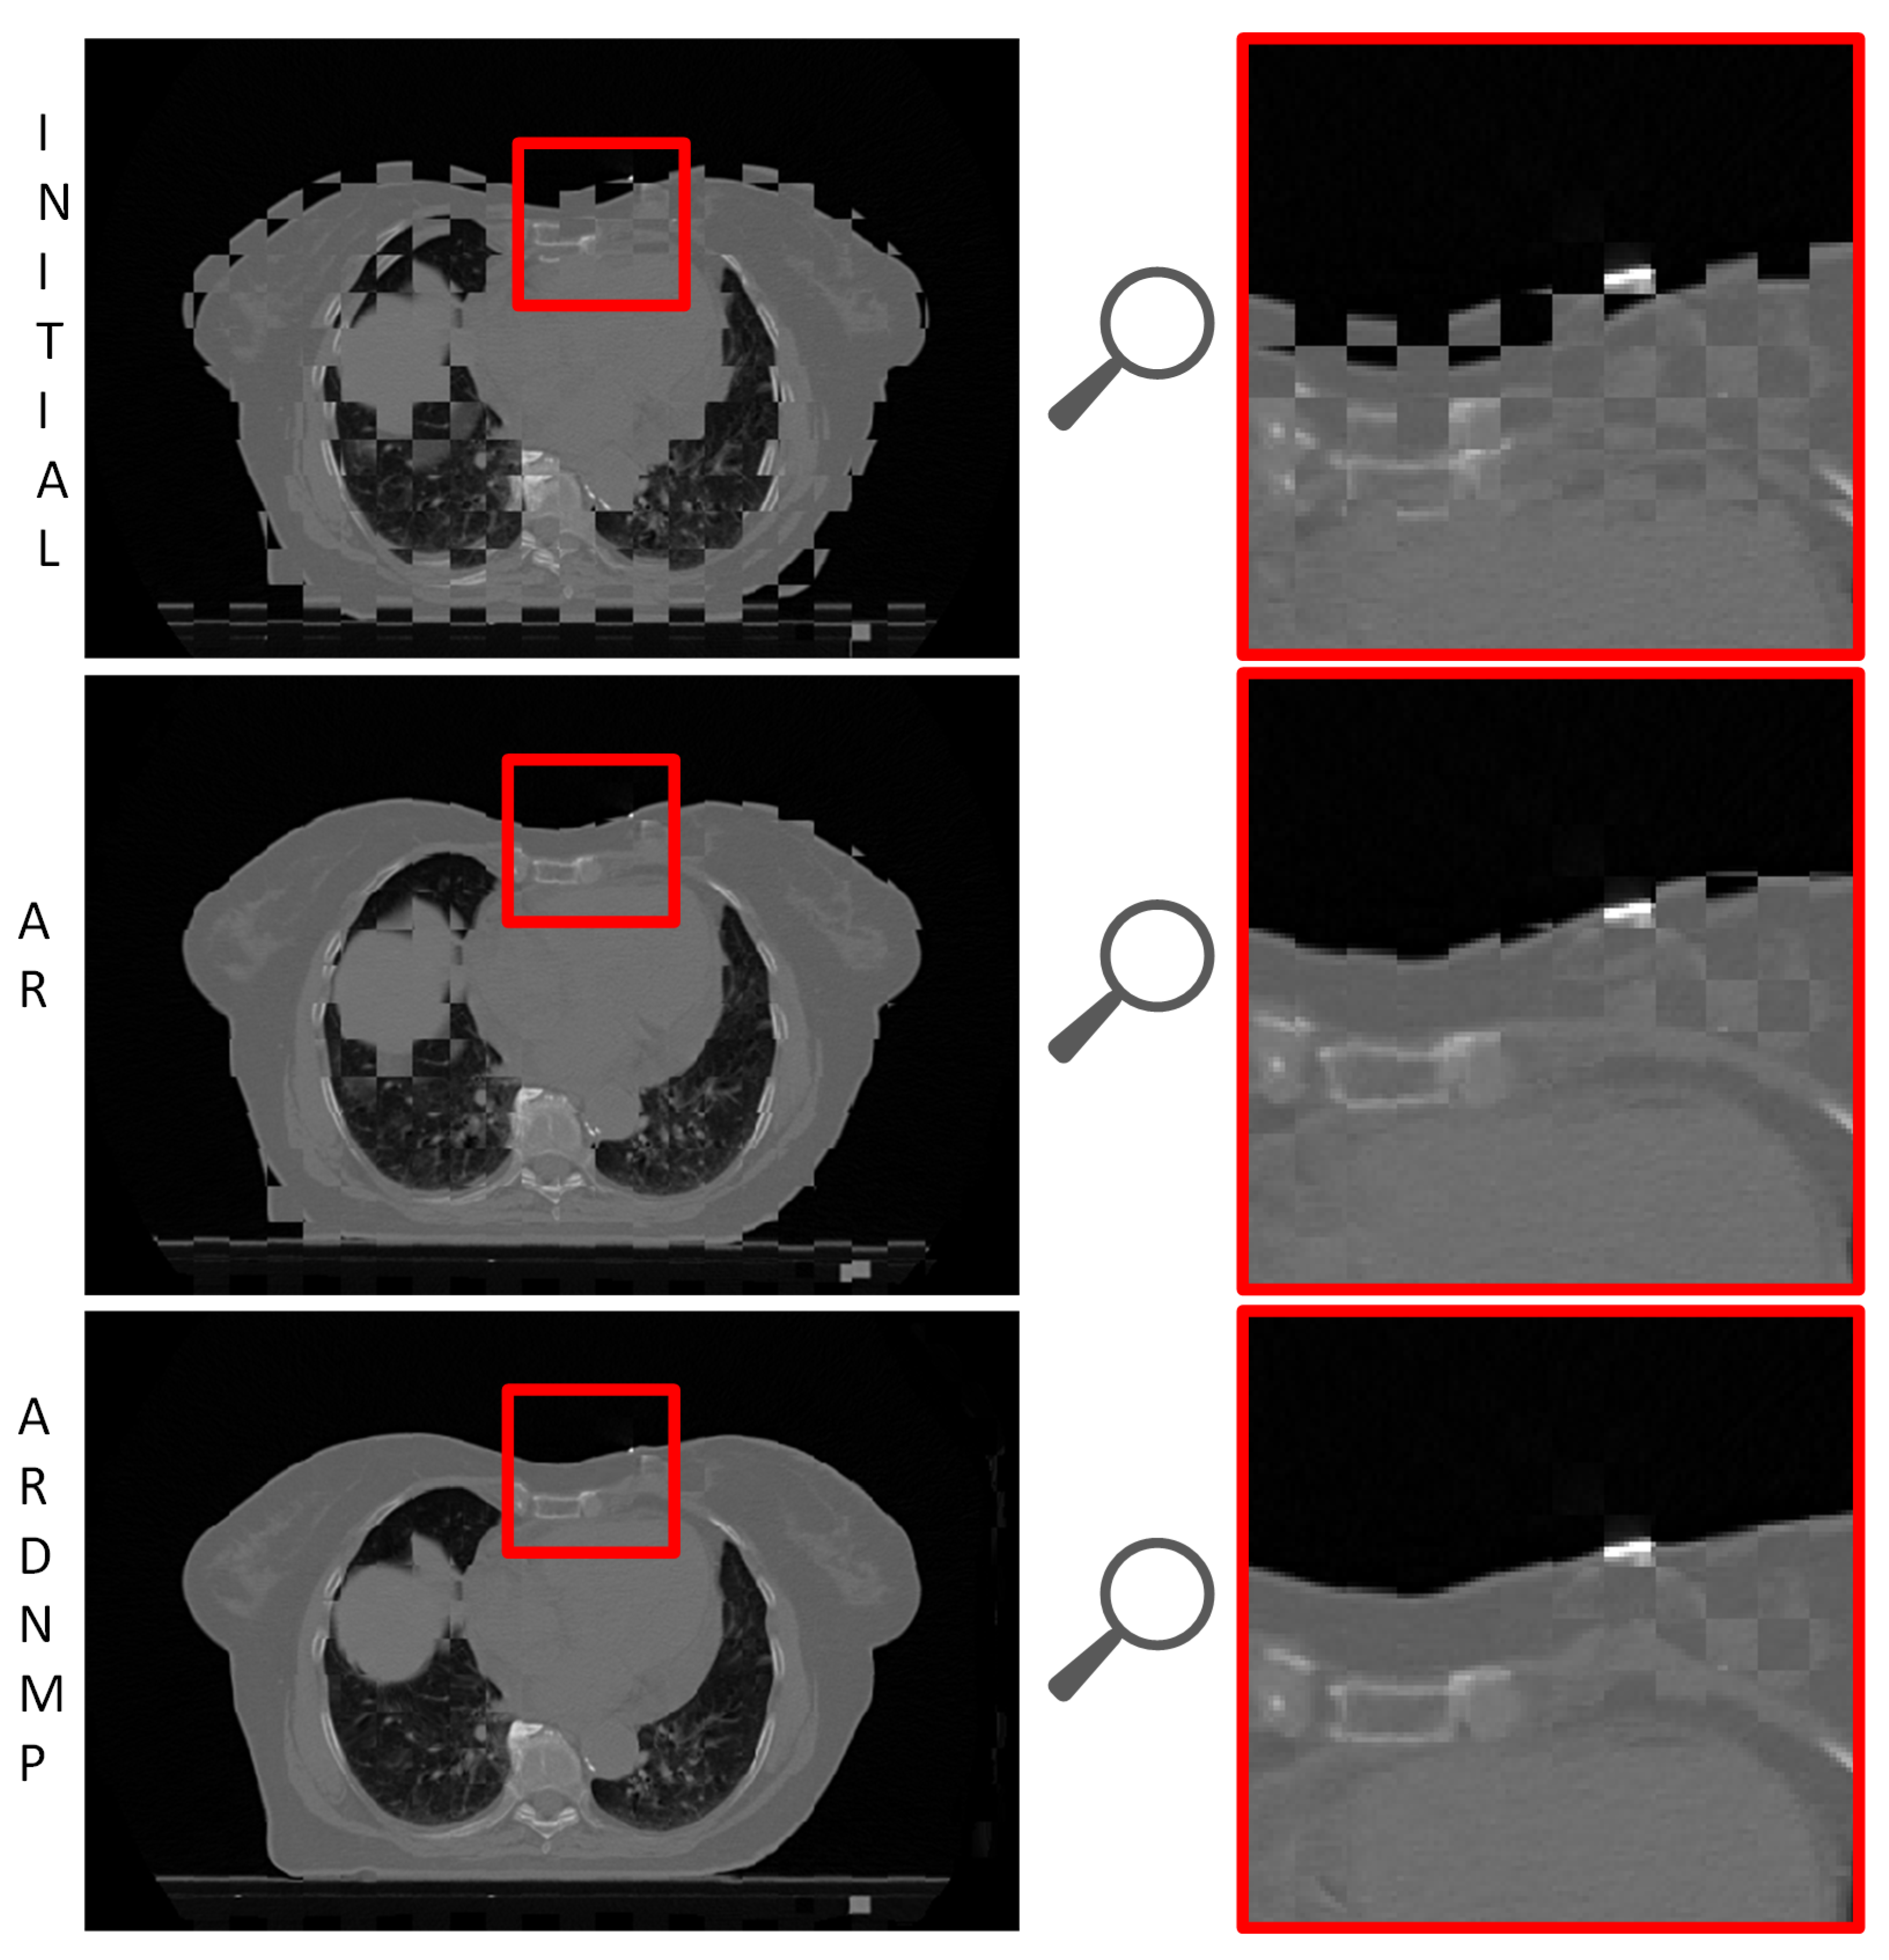

3.3. Visual Assessment